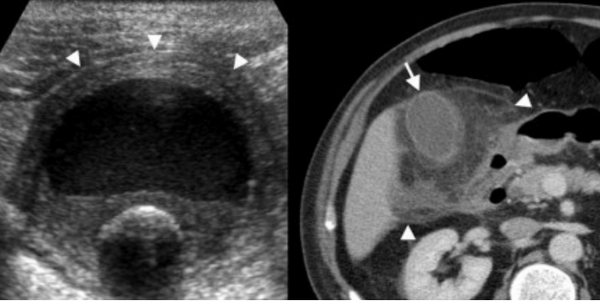

74 — летнему мужчине выполнено УЗИ желчного пузыря. Диагноз: острый некалькулезный холецистит. На левой сонограмме стрелкой указано утолщение стенок желчного пузыря. В просвете желчного пузыря взвесь. На правой сонограмме у того же пациента при исследовании в доплеровском режиме выявлен еще один признак воспаления — гиперемия.

УЗИ и КТ желчного пузыря. Ксантогранулематозный холецистит. Слева на УЗИ визуализируется (помечено стрелками) утолщение стенки желчного пузыря с интрамуральным включением и с камнем в просвете органа. Справа на КТ выявляется утолщение стенки с гиподенсными включениями.